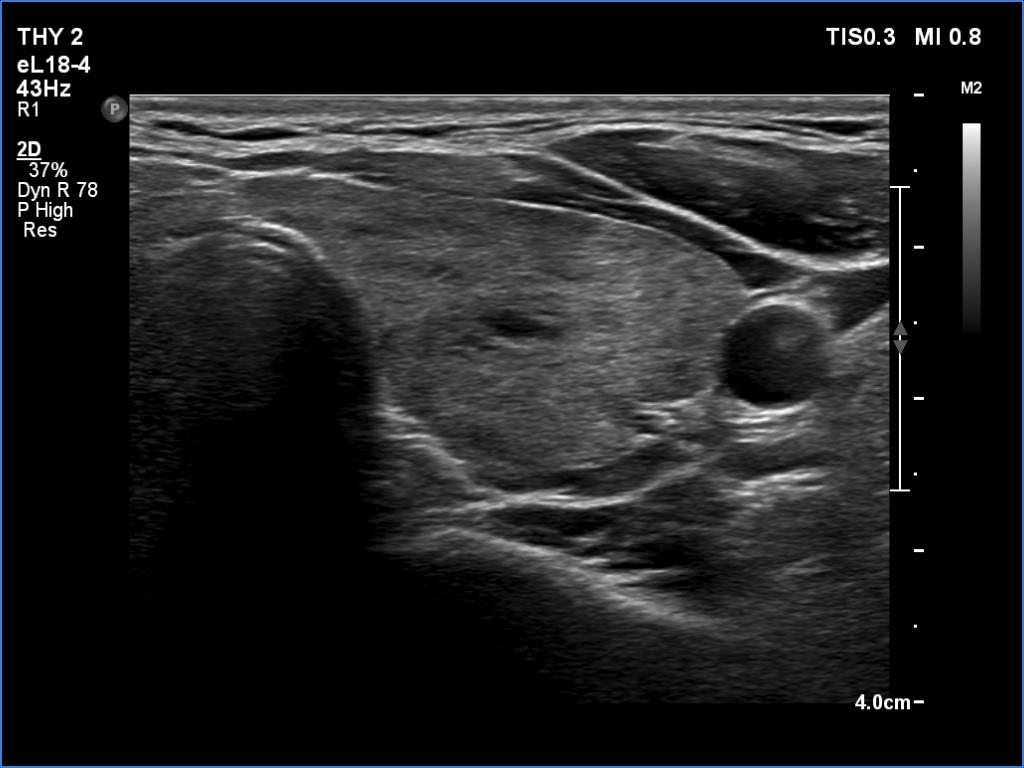

Left lobe, transverse scan

Left lobe, longitudinal scan

Comment.

This is the typical course of a non-relapsing Graves' hyperthyroidism. As the hormone results improve, both the size of the initially enlarged goiter and the degree of hypoechogenicity decrease.